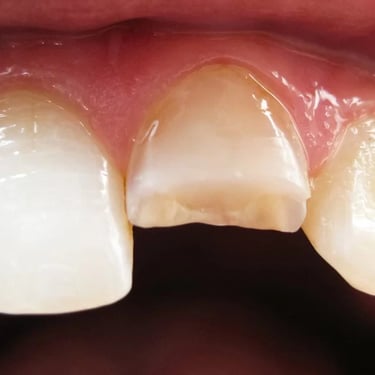

Lesión Traumática Pulpar

Una lesión traumática pulpar es un daño a la pulpa dental debido a un trauma, como un golpe en el diente.

Los pacientes pueden experimentar dolor, sensibilidad y decoloración del diente.

El tratamiento incluye evaluar la vitalidad de la pulpa y, si es necesario, realizar un tratamiento de conducto. Es importante tratar la lesión para evitar complicaciones a largo plazo.